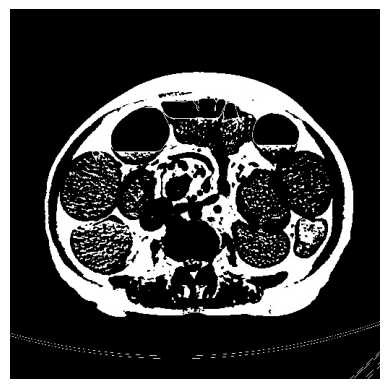

3.1.1 Preprocessing

We extract DICOM (Digital Imaging and Communications in Medicine) slices at the level of the L4 vertebra from the CTE scans along the z-axis using TotalSegmentator. For 2D analysis, we extract the slice at the mean level of L4. For 3D analysis, we extract all slices that contain any portion of the L4 vertebra. A threshold of 0 to -150 Hounsfield Units (HU) (HU range of fat in CT Scans [inproceedings]) is applied to generate a binary mask that includes only fat pixels. Subsequently, we perform one cycle of erosion followed by dilation to remove any additional white lines representing the CT scan machine. This step ensures the proper functioning of our algorithm without significantly altering the fat ratio computation. The boundary and area of the segmented sectors are illustrated in the image below.